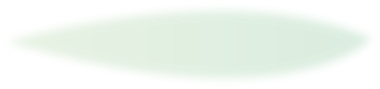

三,他总结出利用中医远端治本的治病理念——

他将《黄帝内经》“上病下治,左病右治”的理念,利用到肘滚技法中,总结出了“头痛滚膝、胃病滚腿”等治病疗法。

将全身的经络联动起来,进一步丰富了肘滚技法的调理手段。